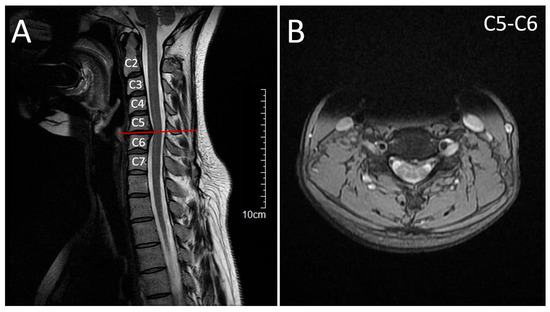

2.1. Patient 1 (Proband)

2.2. Patient 2 (Affected Sibling)